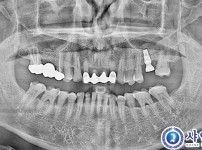

148

뼈이식임플란트 5개 - 스트라우만 록솔리드